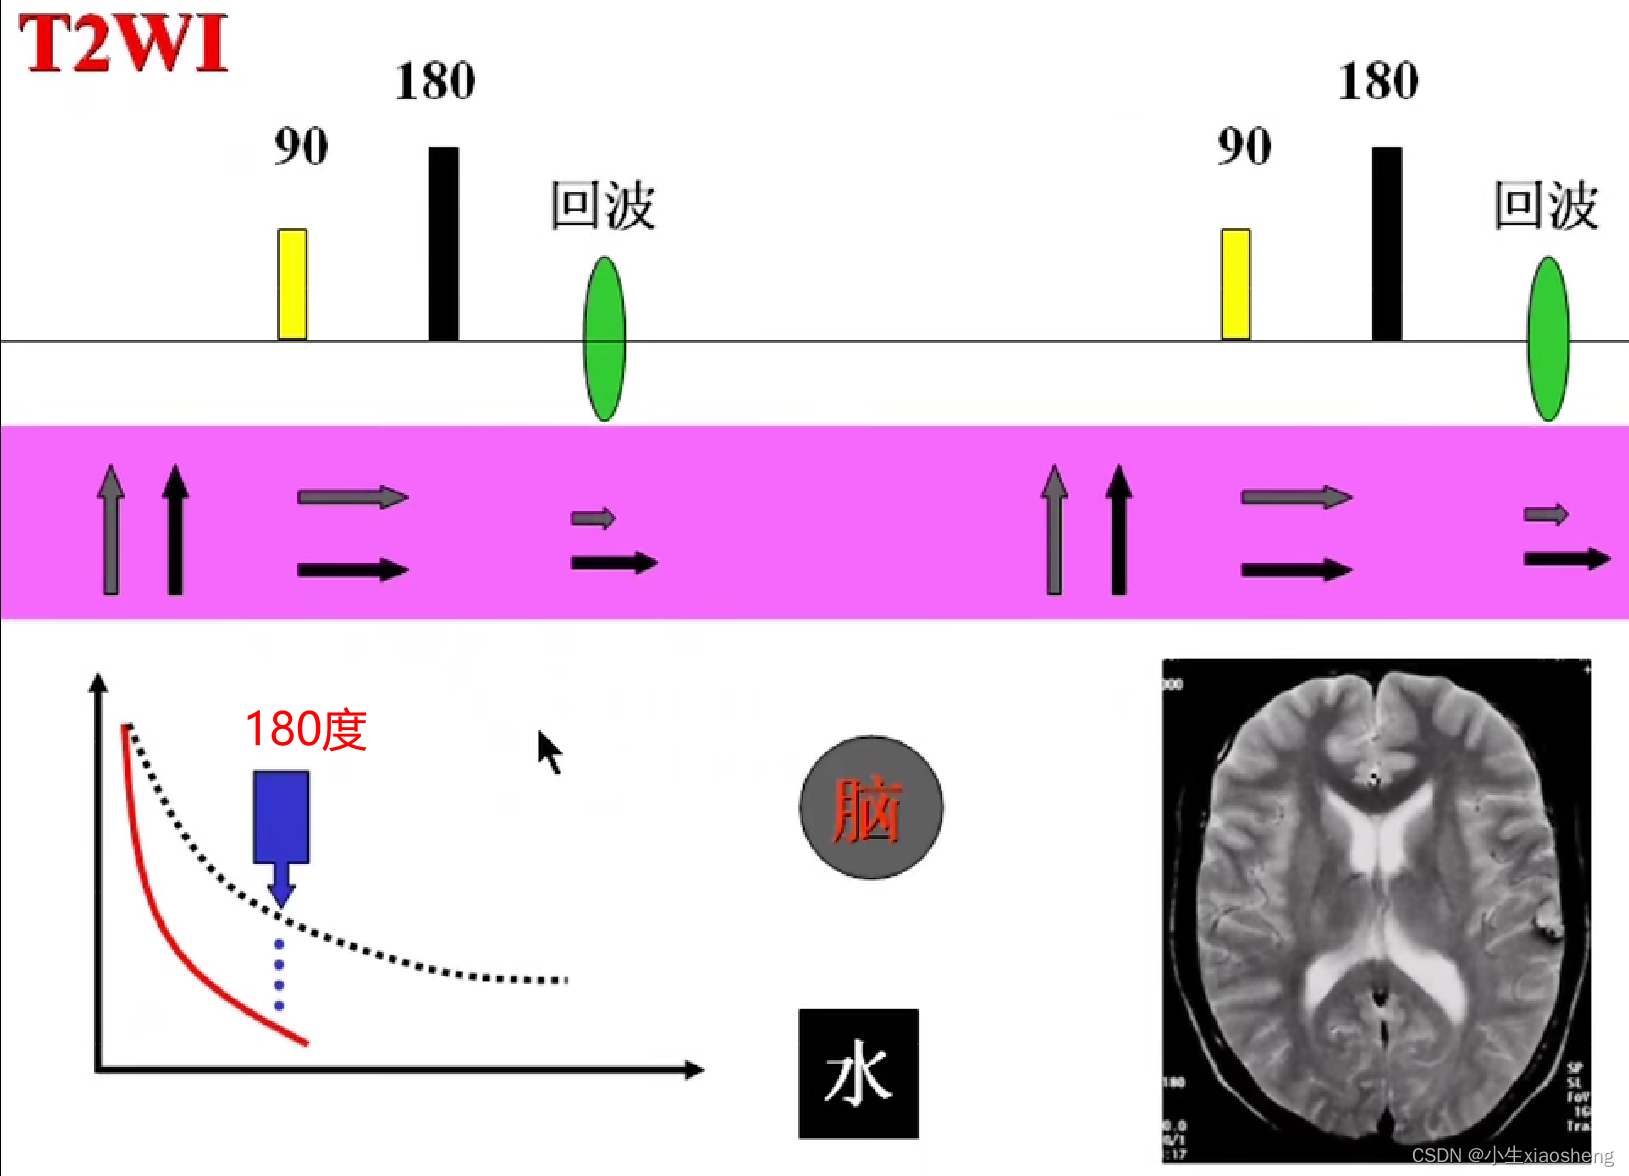

T2(横向弛豫时间):关闭射频脉冲后,质子不再处于同步、同相位状态,指向同一方向的质子散开,导致横向磁化矢量从最大衰减到零。这个过程被称为横向弛豫。

180度的意思就是改变终点的方向,恢复慢的离终点近,恢复快的离终点远,到时候一起到。这样就比原来的弛豫下降的时间要长了。

选择合适长的TE获得最好的T2对比:一般TE选择两种组织生物T2值附近可获得最好的T2对比。